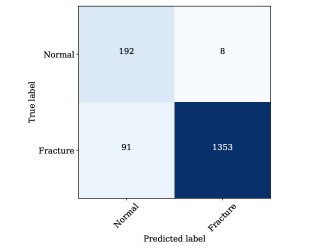

However, it tends to make more errors when classifying images as “Fracture," as indicated by 97 false positives and 1347 true positives. This can be attributed to the nature of medical image analysis, where the cost of missing a “Fracture" (false negatives) may be considerably higher than misclassifying a “Normal" image as a “Fracture" (false positives). YOLOv8m, on the other hand, demonstrates a similar trend but with slightly improved performance when compared to YOLOv8s. It correctly classifies 192 “Normal" images and 1353 “Fracture" images. However, it still makes some errors, with 8 false negatives for “Normal" and 91 false positives for “Fracture". This model appears to strike a better balance between precision and recall for both classes, indicating a more robust classification performance.